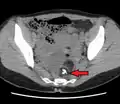

A small (4 cm) dermoid cyst of an ovary, discovered during a C-section

While all ovarian cysts can range in size from very small to quite large, dermoid cysts are not classified as functional cysts. Dermoid cysts originate from pluripotent germ cells (which are present at birth) that differentiate abnormally, developing characteristics of mature dermal cells. Complications exist, such as torsion (twisting), rupture, and infection, although their incidence is rare. Dermoid ovarian cysts which are larger present complications which might require removal by either laparoscopy or laparotomy (traditional surgery).[3][4] Rarely, a dermoid cyst can develop in the vagina.[5][6][7]

The association of dermoid cysts with pregnancy has been increasingly reported. They usually present the dilemma of weighing the risks of surgery and anesthesia versus the risks of untreated adnexal mass. Most references state that it is more feasible to treat bilateral dermoid cysts of the ovaries discovered during pregnancy if they grow beyond 6 cm in diameter.